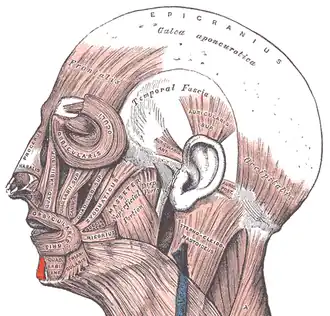

Muscles of the head, face, and neck. | |